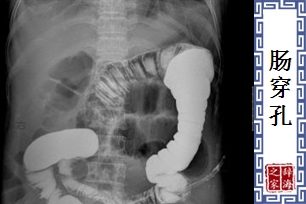

病名。肠壁穿破成孔,粪便等排泄物流入腹腔,导致感染。症状包括呕吐、剧烈的腹痛、脉搏微弱等。

【肠穿孔】 图片鉴赏